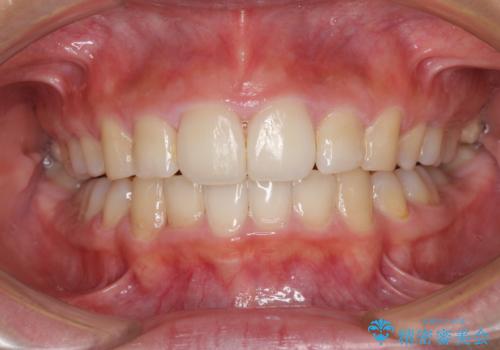

しっかりと通院するようになってからは順調に治療が進み、横顔の印象が変わるほどスッキリとした口元となりました。